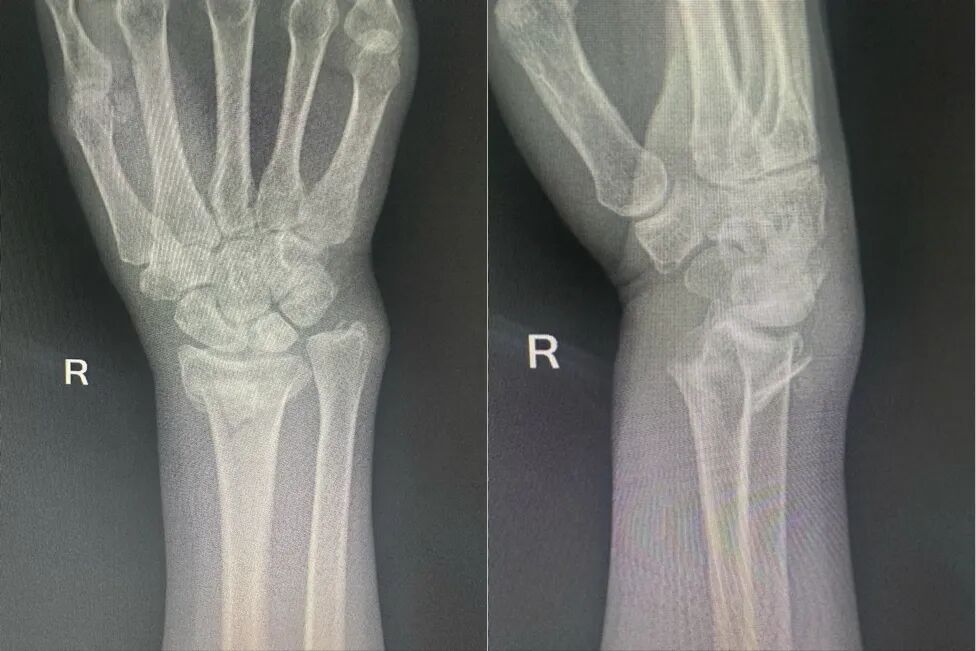

趁着国庆假期,李阿姨与家人来到古城西安旅行,恰逢雨天,老人在游览美景时,因地面湿滑不慎摔倒,右手腕部剧烈疼痛、肿胀变形,活动受限。随行家人紧急送至就近西医医院,X光检查确诊为“右桡骨远端骨折”,建议手术治疗。

图片

复位前